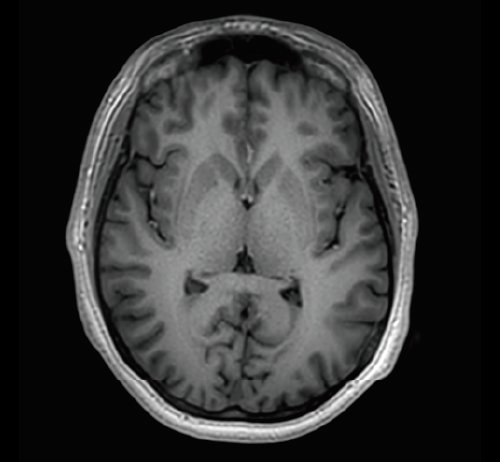

KI-optimiertes Arbeiten und modernste 3T-Technologie machen den Vantage Galan 3T von Canon Medical aus. Canons KI-Anwendung AiCE, kurz für Advanced intelligent Clear-Imagequality Engine, entfernt intelligent das Rauschen und führt zu einer Verbesserung des SNR (Signal-Rausch-Verhältnis). Mit Hilfe der Deep Learning Technologie gelingen besonders klare und deutliche Bilder. Insgesamt ermöglicht die KI-Unterstützung des Vantage Galan 3T somit nicht nur eine höhere Auflösung der Bilder, sondern verkürzt in vielen Fällen auch die Aufnahmezeit.

Mit der PURERF-Technologie und der PUREGradienten-Technologie werden das SNR um bis zu 20% verbessert und Diffusionsbilder optimiert.